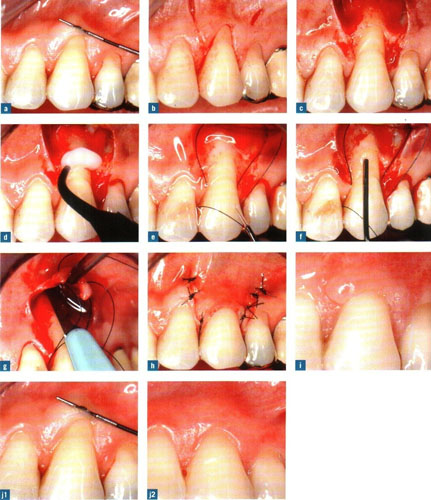

rejeneratif periodontoloji ameliyatı

Ayrıca genel ve lokal dişeti abseleri oluşabilir. Bu sorunun tedavisinde dişetinin açılarak dişik kök yüzeyinin temizlenmesi, civardaki iltihaplı dokunun (granülanyon dokusu) temizlenmesi ve kliniğimizde uyguladığımız yöntemle, o boşluklara yapay kemik + minematriks proteini (Emdogain (R) ) uygulaması yapılarak 6-8 ay sonra operasyon bölgelerinde yeniden alveol kemiği oluşumu sağlanmakta ve bu yolla belkide çekilecek bir diş ağızda tutulmaktadır.

1) Dişeti cebinde azalma 2) Dişeti iltihaplarının ortadan kalkması 3) Ataşman (dişetinin yeniden dişe yapışması) kazancı da operasyonun başarısının kanıtı olarak ortaya çıkar.